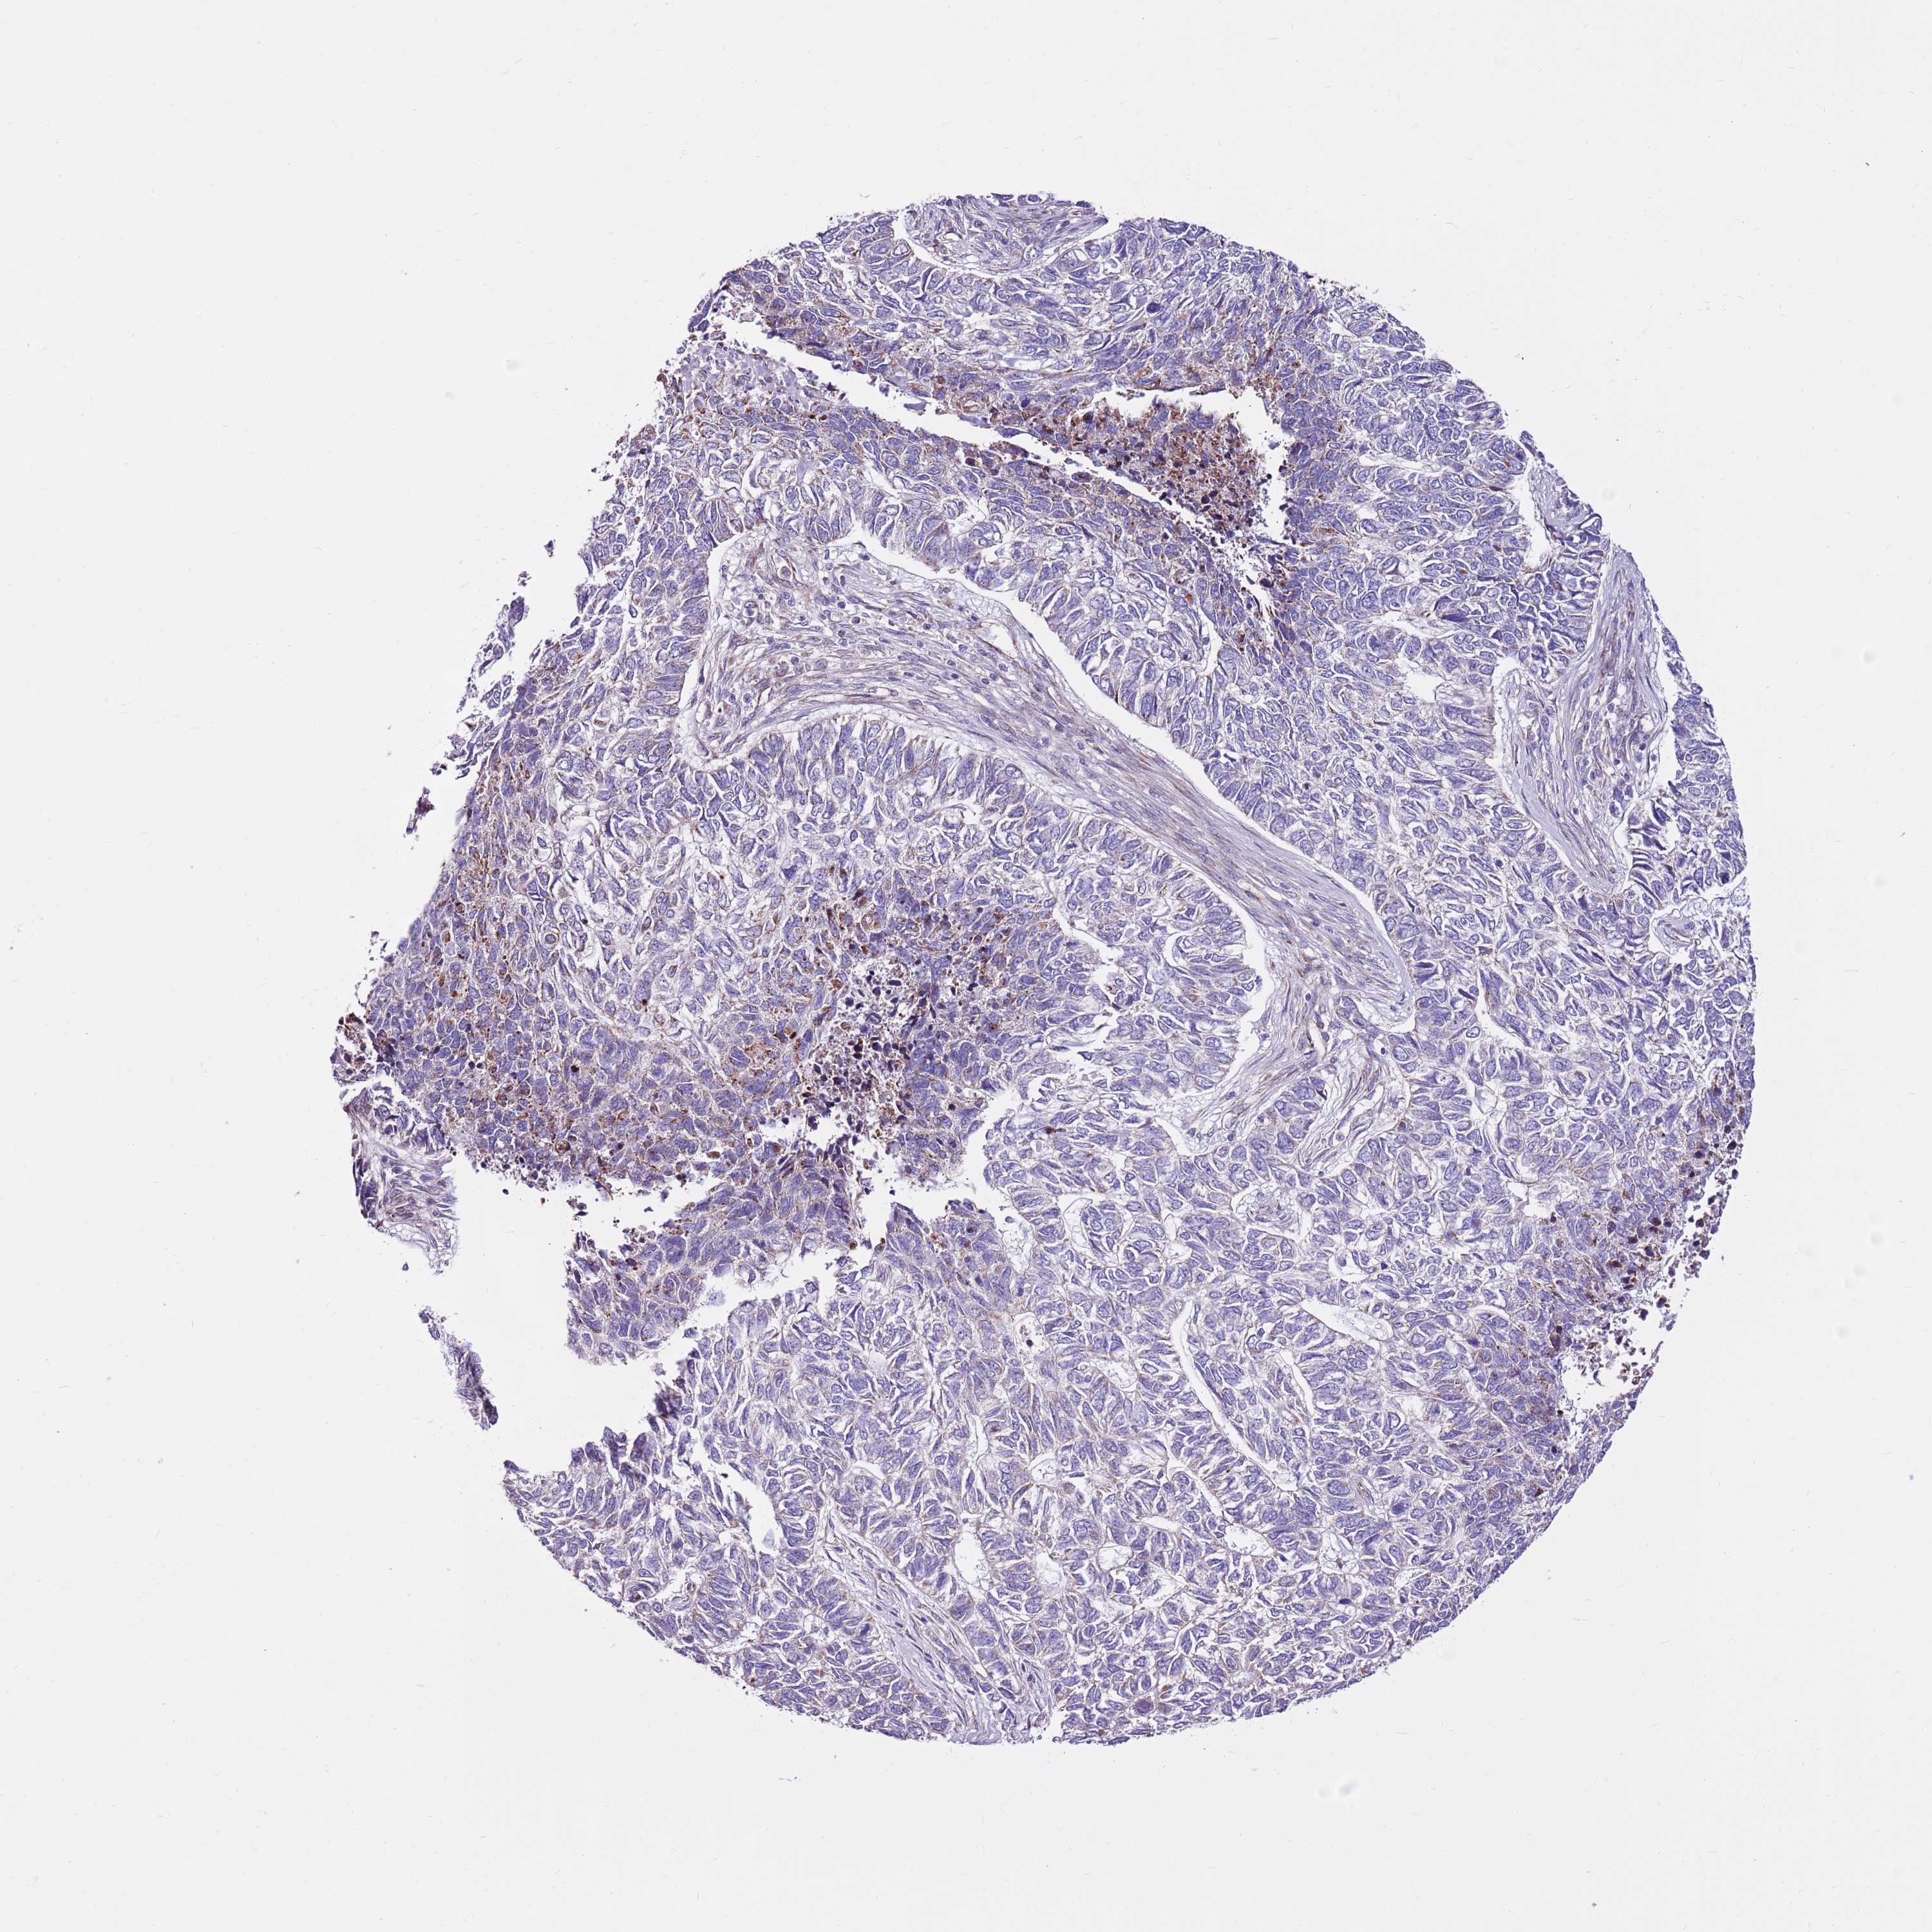

SKIN CANCER - Protein expressioni

A mouse-over function shows sample information and annotation data. Click on an image to view it in a full screen mode. Samples can be filtered based on level of antibody staining by selecting one or several of the following categories: high, medium, low and not detected. The assay and annotation is described here.

Antibody stainingi

Antibody staining in the annotated cell types in the current human tissue is reported as not detected, low, medium, or high, based on conventional immunohistochemistry profiling in selected tissues. This score is based on the combination of the staining intensity and fraction of stained cells.

Each image is clickable and will lead to virtual microscopy that enables deeper exploration of all samples and also displays staining intensity scores, fraction scores and subcellular localization as well as patient and tissue information for each sample.

Antibody HPA041062

Antibody HPA045473

Basal cell carcinoma

Squamous cell carcinoma, NOS

Squamous cell carcinoma, metastatic, NOS